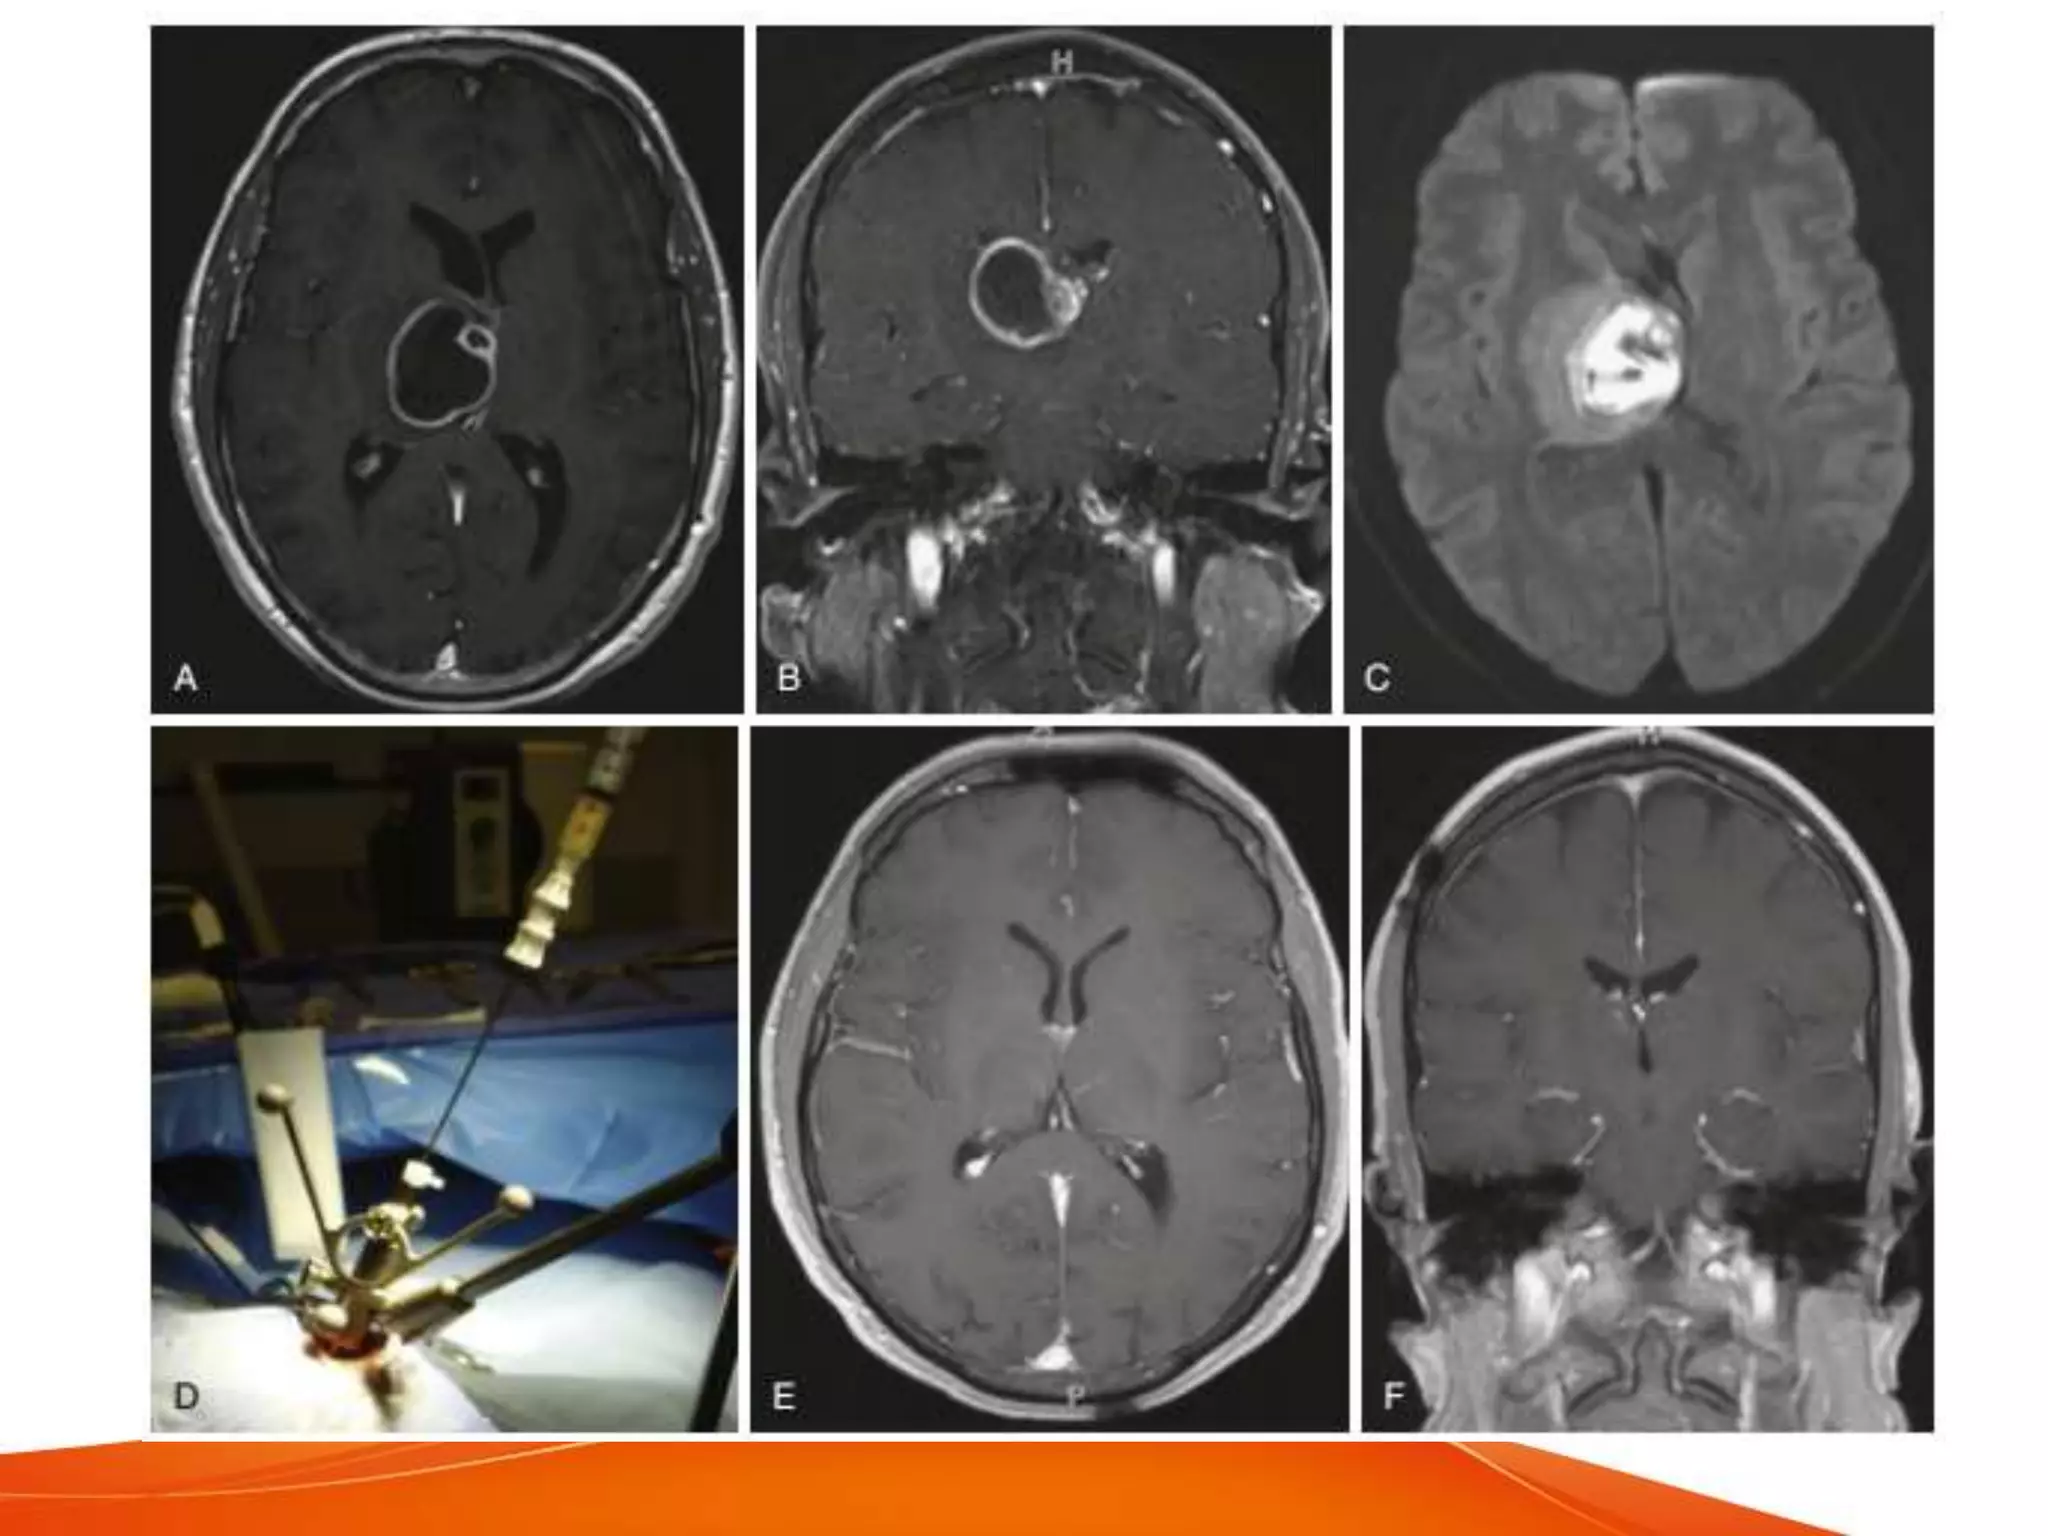

ASPIRATION

• provides specimens

• low surgery related morbidity and mortality

• post aspiration recurrence - upto 32%

• CT guided aspiration accurate within a few

mm with yield of 95%

• highly effective in definitive drainage of

abscess

• preferred treatment for deep seated

lesions or eloquent areas

• suitable for

– brain stem

– thalamus

– basal ganglia

• stereotactic drainage - can drain multiple

abscesses, with prolonged medical

therapy is effective

• frameless neuronavigation - best

technique to localise

• less chance of seizures and other

sequelae

• Ultrasound guidance

– real time

– reliable

– fewer risks

– minimally invasive and accurate

• other methods

– endoscoic stereotactic aspiration and

irrigation

• precise localisation, minimal craniotomy, multiple

lesions addressed